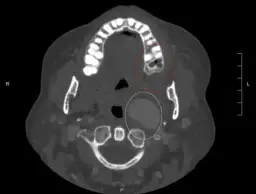

Usunięcie zębów mądrości, znanych również jako ósemki, to procedura, która może wiązać się z wyższymi kosztami niż standardowe ekstrakcje. Koszt usunięcia zęba mądrości w Polsce zazwyczaj zaczyna się od 700 zł i może sięgać nawet 1100 zł w przypadku dolnych ósemek. Wysoka cena wynika z złożoności zabiegu, który często wymaga chirurgicznego dostępu do zęba, zwłaszcza gdy jest on zatrzymany lub nieprawidłowo wyrżnięty.

W przypadku zębów mądrości, które są w pełni wyrżnięte i łatwe do usunięcia, koszt może być niższy, ale nadal wyższy niż w przypadku prostych ekstrakcji innych zębów. Dodatkowe czynniki, takie jak lokalizacja gabinetu, doświadczenie stomatologa oraz potrzeba znieczulenia, również mogą wpływać na ostateczną cenę. Warto skonsultować się z dentystą, aby uzyskać dokładną wycenę przed zabiegiem.